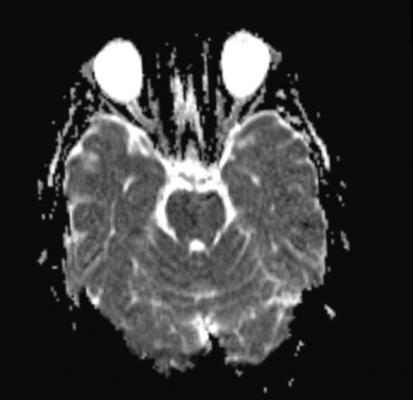

15+ Vascular Disease Brain Symptoms UK. Arteries supplying oxygen and nutrients to the brain are often damaged or deformed in these disorders. The term cerebrovascular disease includes all disorders in which an area of the brain is temporarily symptoms of a tia may be similar to stroke, but they resolve quickly.

Peripheral vascular disease, also called pvd, refers to any disease or disorder of the circulatory system outside of the brain and heart. The term cerebrovascular disease includes all disorders in which an area of the brain is temporarily symptoms of a tia may be similar to stroke, but they resolve quickly. Vascular dementia symptoms vary, depending on the part of your brain where blood flow is impaired.

Shooting pains, numbness, or tingling in the. Risk factors and causes of pvd are having diseases and conditions like diabetes, high blood pressure, arteritis, and infection. Almost always, symptoms are caused by the leg muscles not getting. Vascular dementia, sometimes called vascular cognitive impairment, is the second most common cause of dementia after alzheimer's disease.